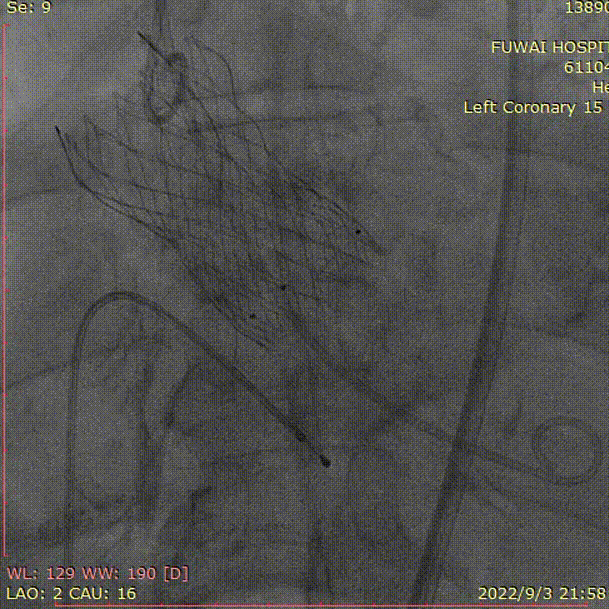

六、急诊TAVR操作过程

1、冠脉造影和抉择急诊PCI和急诊TAVR

4、植入VenusA-Plus  L29,术后造影冠脉显影良好

完全释放